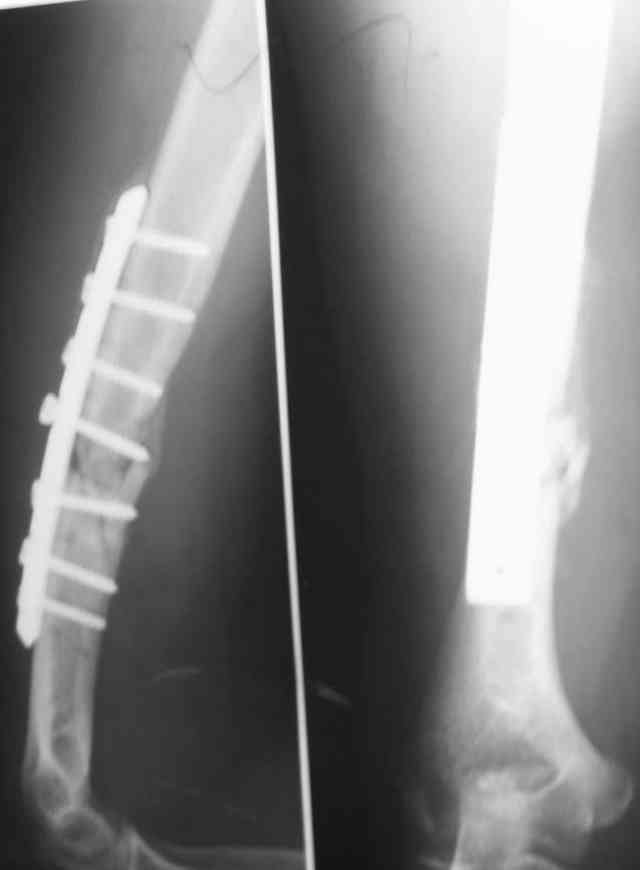

Штифт - отвисание проксимального отдела - накостный остеосинтез, нагноение, АФВ с ревизиями раны, опять пластина и снова нестабильность. Была удалена пластина и выполнен БИОС штифтом ChM (ДЕОСТ). Через 2 нед. пациент сел за руль и вышел на работу. Причем так и работает до сих пор уже 1,5 года, хотя полного сращения мы вроде бы не достигли ( снимки пришлю позже) - пациент не приходил на осмотры, общался только по телефону.

Второй пациент перенес два неудачных накостных остеосинтеза на фоне пареза лучевого нерва. Была удалена пластина и выполнен БИОС штифтом ChM (ДЕОСТ) - это была наша первая операция БИОС.